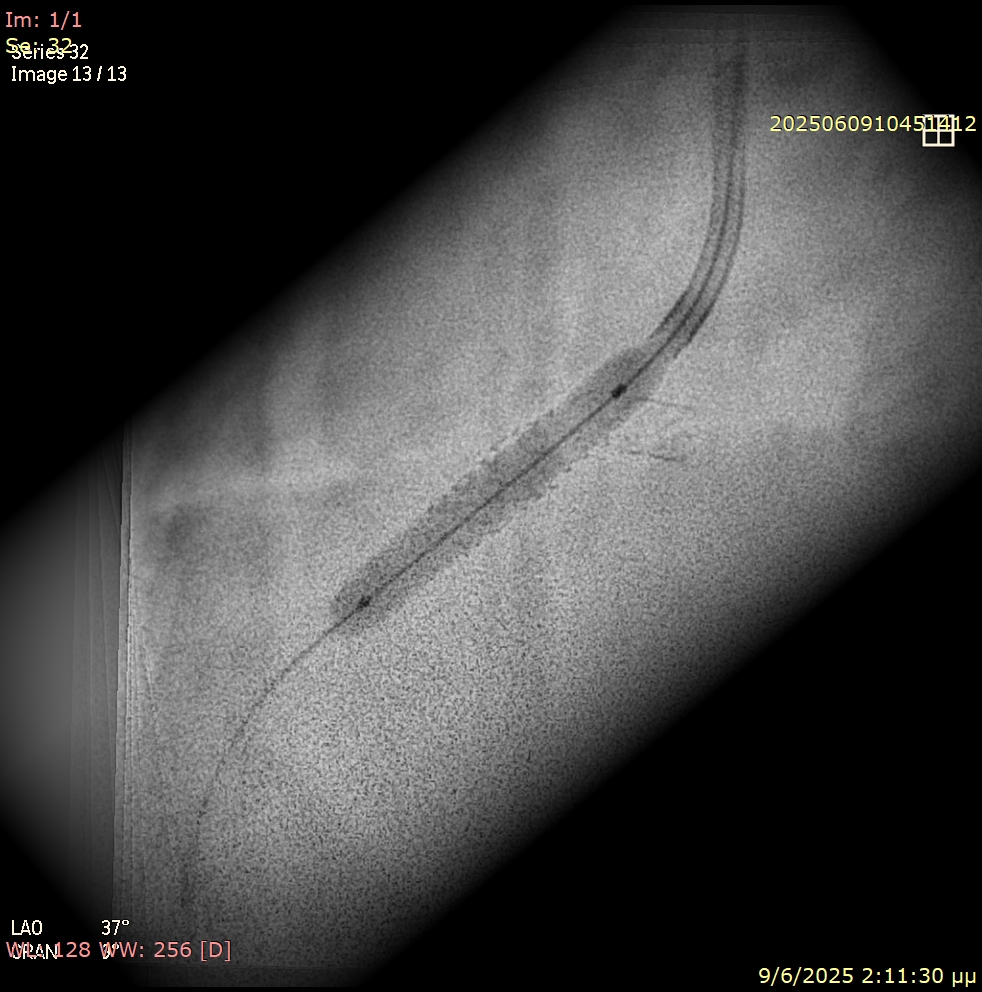

Unexpected resistance was encountered while attempting to deliver balloons across the ostial segment (Figure 2). Suspecting an underlying issue, the angiographic projection was modified to a more cranial view. This revealed that a significant portion of the prior stent was protruding into the aorta, obstructing device passage (Figure 3).

Using progressive balloon dilatation (non-compliant 3.0 x 15 mm, 3.5 x 15 mm, and 4.0 x 15 mm) followed by a 3.5 x 10-mm scoring balloon (Figure 4), we successfully fenestrated the stent strut. To avoid placing a second metal layer at the ostium and prevent double stenting, we concluded the procedure with a 3.5 x 20-mm paclitaxel-coated balloon (Figures 5 and 6, Video). The final result was good, with Thrombolysis in Myocardial Infarction-III flow (Figure 7). Dual antiplatelet therapy (DAPT) with aspirin 100 mg once daily and clopidogrel once daily was prescribed to the patient. Given the low bleeding risk based on the PRECISE-DAPT score and the assumption that forming a fenestration at the upper part of the stent would place the patient at high ischemic risk, we decided to continue the duration of DAPT beyond 1 year.